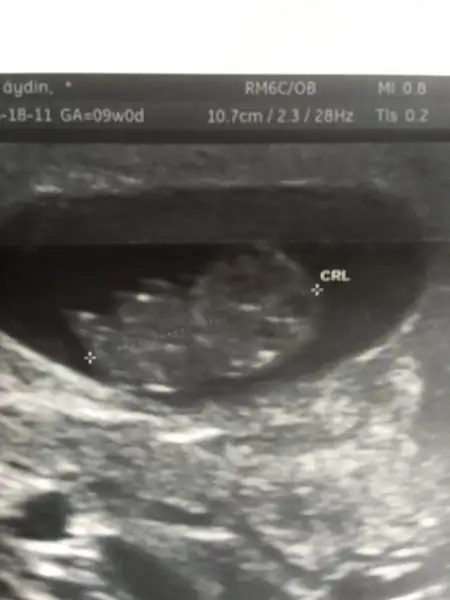

hakkımıza hayırlısı olsun canım ben erkek olsun istiyorum içime öyle doguyorerkeğe benziyor ama kesin bi şey söylemek için 2 hafta var dedi

Böyle belli olmuyor ki normal usg yok mu canım?

ben canım 1 hafta gerideyim sat a göre...Kızlar geç döllenme ya da dış gebelik yaşayan var mı? Ya da 6. haftada karından bebeği gözükmeyen ?

Ne zaman gördünüz bebeği? 6. haftada kesenin boş gözükmesi normal mi acaba? Çok yakın bir arkadaşım şuan böyle bir durum yaşıyor doktor kürtaj demiş ama çok küçük biryerde yaşadığı için ben çokta güvenemedim açıkçasıben canım 1 hafta gerideyim sat a göre...